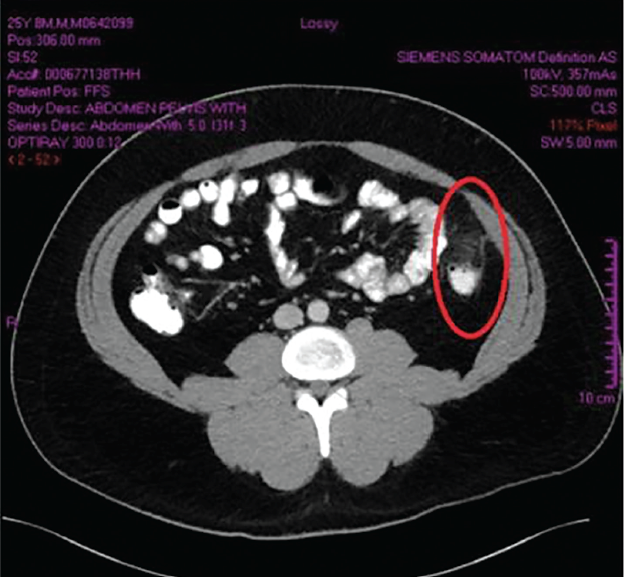

Ahmed Raziuddin, MD; Mohammed Hassan-Ali, MD, MSc; Mohemmad Abbas, MD

A 25-year-old man presented with a 4-day history of sudden pain in the left lower quadrant, leading to the primary care provider's initial diagnosis of diverticulitis.